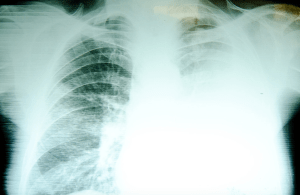

An x-ray of a miner’s internal organs reveals a prognosis of silicosis, a chronic condition in which silica enters the lungs and causes scarring.